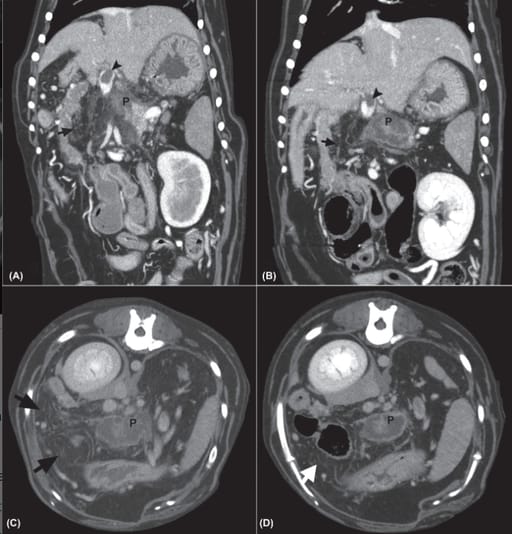

A, Initial CTA, venous phase, dorsal plane reconstruction (window width 450, window level 90). The pancreas (P) is heterogeneously contrast enhancing with surrounding mesenteric changes (arrow). Note the portal vein thrombus (arrowhead). B, Repeat CTA (3 days later), CTA, venous phase, dorsal plane reconstruction (window width 450, window level 90). The pancreas continues to be heterogeneously contrast enhancing (P) but has better defined margins. The mesenteric changes have improved (arrow). Note the continued presence of the portal vein thrombus (arrowhead). C, Initial CTA of same patient, delayed phase, transverse plane image (window width 450, window level 90). Note the mesenteric changes (arrows) surrounding the heterogeneously contrast enhancing pancreas (P). D, Repeat CTA, delayed phase, transverse plane image (window width 450, window level 90). Note the improved mesenteric changes (arrow) surrounding the pancreas (P)

All dogs exhibited pancreatic enlargement and heterogeneous contrast enhancement on initial CTA, with peri-pancreatic fat stranding in 73% of cases. Portal vein thrombosis was observed in 55%. The only statistically significant difference between initial and repeat CTA was improvement in fat stranding (P = .045). No significant changes were detected in pancreatic size, contrast enhancement, or presence of portal vein thrombosis.